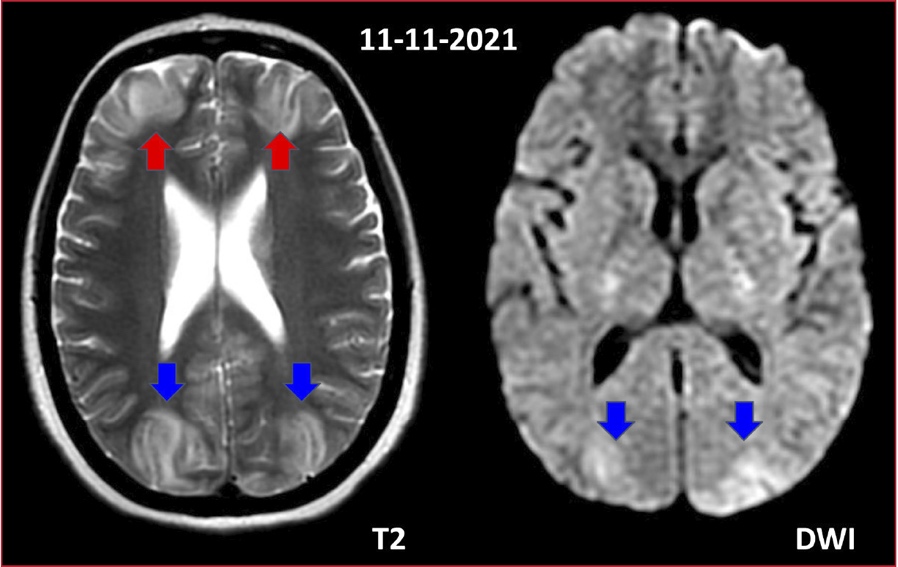

Figura 1. Resonancia magnética de cerebro.

Cambios de señal hiperintensos en secuencia T2,corticales, en la región fronto-parieto-occipital,

bilaterales, simétricos (flechas rojas y azules),sin restricción significativa

a la difusión, como así también, en el sector postero-inferior de ambos

hemisferios cerebelosos.